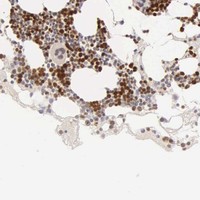

Enhanced - Orthogonal

Antibody staining mainly consistent with RNA expression data across 44 tissues.

HIGH EXPRESSION

Bone marrow

RNA expression: 45.7 nTPM

LOW EXPRESSION

Cerebral cortex

RNA expression: 0.6 nTPM